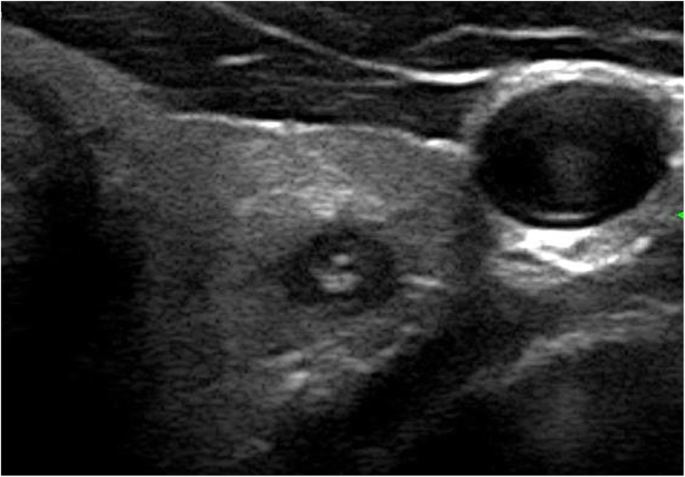

The results of the multivariate logistic regression analysis for US characteristics are summarized in Table 3. The proportion of MTMCs with ovoid to round shapes (Figs. 1 and 2) was higher than that of PTMCs (Fig. 3) (54.35% vs 9.56%, P = 0.007), but PTMCs with taller-than-wide shapes (Figs. 4 and 5) were much more common than MTMCs with the same shape (Fig. 6) (59.56% vs 19.57%, P = 0.000). An unclear boundary seemed to be more commonly detected in PTMCs (Fig. 3) than in MTMCs; however, there was no significant difference (86.03% vs 43.48%, P = 0.188). There were more nodules with a > 50% solid composition in the MTMC group than in the PTMC group (13.04% vs 1.47%, P = 0.032). Calcifications were not commonly observed in either group; when they occurred, macrocalcifications were more often seen in MTMCs (Fig. 2) than in PTMCs (Fig. 3) (21.74% vs 6.62%, P = 0.004). Microcalcifications were more frequently detected in PTMCs (Fig. 4), although there was no significant difference (10.87% vs 29.41%, P = 0.214). Hypervascularity was observed in 58.70% of MTMCs but only in 19.85% of PTMCs (P = 0.000).